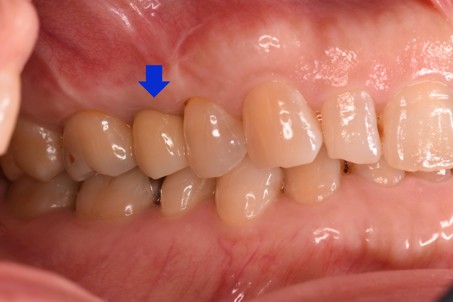

治療前

治療後 ![]() |

長期間、歯が無いままになっていたため隣の歯が動いてきてしまっており新しく歯を入れる隙間が減ってきている状態でした |